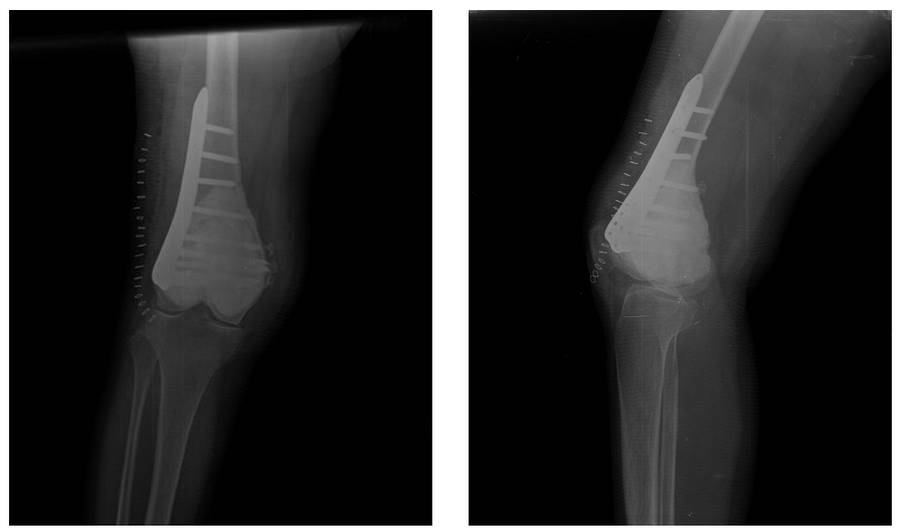

Ameliyat Sonrası: Röntgende çimento ve plak uygulanımı görülmekte